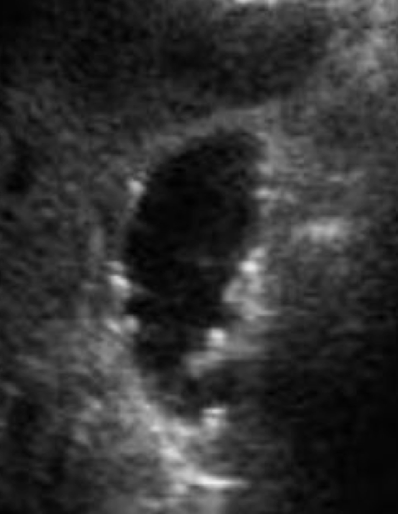

gallbladder carcinoma

primary carcinoma is rare but have a mortality rate of 100%

high association with cholelithiasis (in 80%-90% of cases)

MC in women older than 60 y/o

tumor arises in GB body

GB tumor is usually columnar cell adenocarcinoma

SONO: gallbladder carcinoma

heterogeneous or semi-solid soft tissue mass centered in the GB

thickened and irregular wall

adjacent liver heterogeneous due to invasion

dilated biliary ducts (“bil-dil”)

??

heterogeneous mass in GB

adjacent heterogeneous liver

GB mass —> “bil-dil”